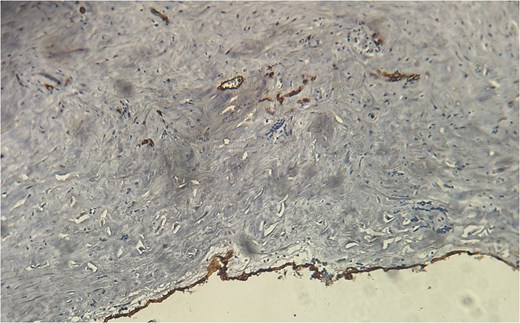

A 60-year-old Moroccan female with no significant medical history presented with chronic periumbilical pain lasting several months, without associated digestive or systemic symptoms, and preserved general condition. Clinical examination revealed periumbilical tenderness. Abdominal ultrasound was unremarkable, prompting an abdominopelvic CT scan, which identified a retroperitoneal inter-aortocaval cystic lesion measuring 86 mm. Surgical exploration revealed a large cystic mass in the mesentery of the small intestine, which was entirely excised. Histopathological examination showed variable-sized cystic cavities with a lymphatic appearance (Fig. 1), lined by flattened and regular endothelium. Some cavities contained pale eosinophilic material interspersed with lymphocytes and areas of red blood cells (Fig. 2). The interstitial tissue exhibited lymphocytic and plasmacytic inflammatory infiltrates. Immunohistochemistry confirmed the lymphatic nature with positivity for Podoplanin/D2–40 (Fig. 3) and CD34 (Fig. 4) and negativity for calretinin (Fig. 5). The patient’s postoperative course was uneventful.

Histopathological examination showing cystic cavities of varying sizes lined by flattened endothelium.